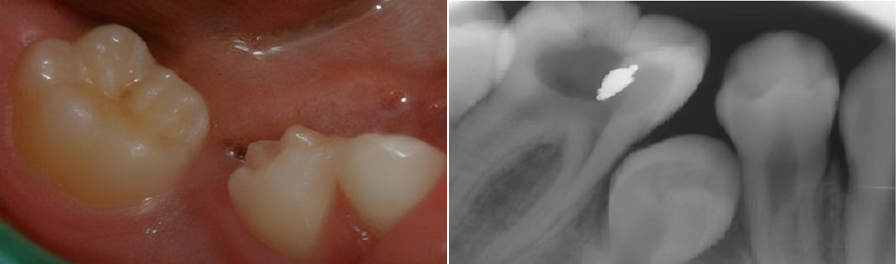

Süt dişlerinde oluşan çürükler zamanında tedavi edilmezse, enfeksiyon gelişebilir ve alttaki daimi dişleri etkileyebilir. Yukarıdaki görüntüler, erken dönemde müdahale edilmeyen diş çürüklerinin klinik ve radyografik görünümünü göstermektedir.